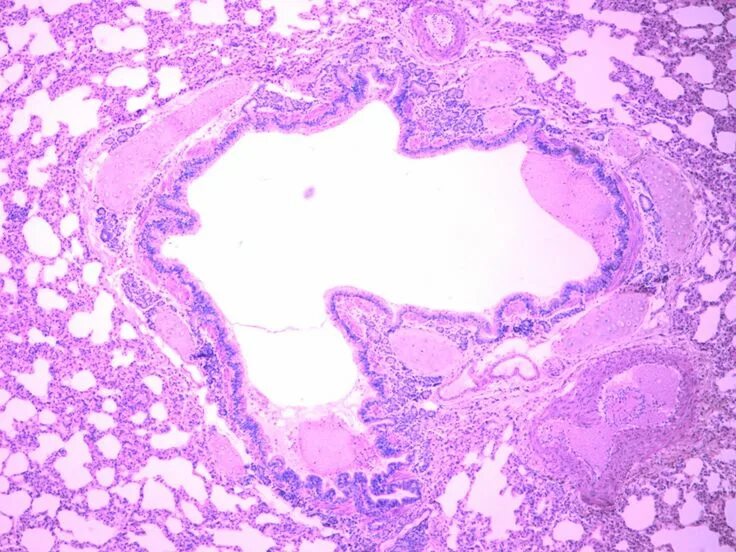

Д гистология